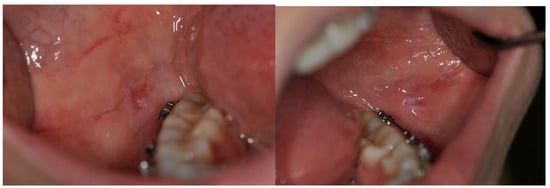

- According to the types and lesions pattern, oral mucosa pathologies are observed in different sites of oral cavity, both in single or multiple localizations and both symmetrically and non-symmetrically.